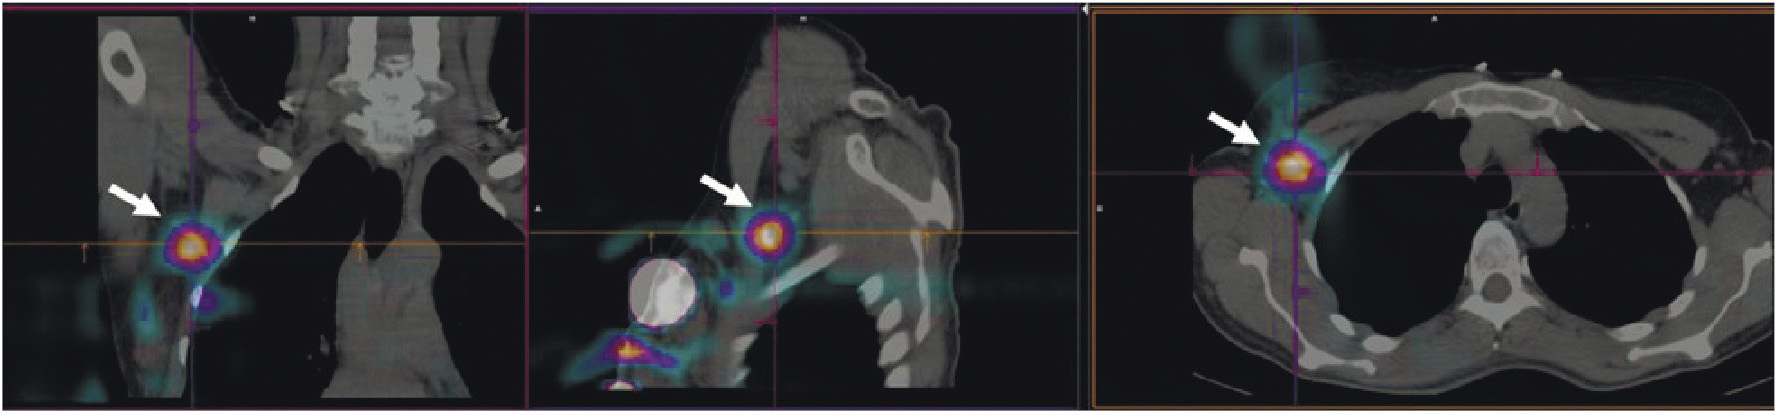

В НИИ онкологии Томского НИМЦ завершены первые фазы клинических исследований нескольких меченных технецием-99м каркасных белков (DARPin, ADAPT, Affibody), обладающих высокой аффинностью к рецептору эпидермального фактора роста второго типа (HER2/neu). Все препараты показали хорошую эффективность определения гиперэкспрессии рецептора HER2/neu при раке молочной железы и стадировании заболевания (рис. 1) [10, 11]. Кроме того, установлена возможность проведения ОФЭКТ/КТ с препаратами на базе скаффолдов для оценки эффекта терапии (рис. 2). Помимо основы РФЛП для диагностики злокачественных новообразований, каркасные белки могут служить вектором доставки при создании таргетных соединений для лечения злокачественных новообразований с гиперэкспрессией рецептора HER2/neu [13].

Рис. 2. ОФЭКТ/КТ-изображение пациентки с HER2/neu-позитивным раком правой молочной железы до начала лечения, выполненное через 2 ч после введения 99mTc-DARPIN-G3 (а), стрелками обозначены первичная опухоль (SUVmax = 3.1), метастазы в лимфатические узлы (SUVmax = 8.8) и кости; ОФЭКТ/КТ-изображение той же пациентки после двух курсов терапии транстузумабом через 2 ч после введения 99mTc-DARPIN-G3 (б), стрелками обозначена первичная опухоль (SUVmax = 0.55), метастазы не визуализируются